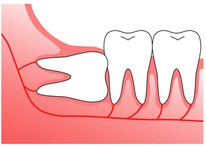

親知らず(智歯)の種類

正常な智歯

まっすぐキレイに生えている状態。

まっすぐキレイに生えている状態。完全埋伏智歯

歯ぐきの中に完全に埋まってしまっていて表面には出ていない、見えない状態です。親知らずがある部分が腫れている、痛みがある、他の歯や顎関節への影響がある場合は抜歯を検討する必要があります。

歯ぐきの中に完全に埋まってしまっていて表面には出ていない、見えない状態です。親知らずがある部分が腫れている、痛みがある、他の歯や顎関節への影響がある場合は抜歯を検討する必要があります。水平埋伏智歯

親知らずが横向きに生えている状態です。横向きに生えているために歯を圧迫して歯並びに影響を与えたり、歯茎などの腫れや痛みの原因になることがあります。年齢を重ねたり、歯磨きがきちんとできていないとより症状が出やすくなるので、早めに抜歯をすることをお勧めしています。

親知らずが横向きに生えている状態です。横向きに生えているために歯を圧迫して歯並びに影響を与えたり、歯茎などの腫れや痛みの原因になることがあります。年齢を重ねたり、歯磨きがきちんとできていないとより症状が出やすくなるので、早めに抜歯をすることをお勧めしています。半埋伏智歯

歯ぐきから親知らずが一部だけ出ている状態です。周りの歯への影響、むし歯や歯周病のリスクが高くなります。歯科医師と相談をして抜歯をすることを推奨します。

歯ぐきから親知らずが一部だけ出ている状態です。周りの歯への影響、むし歯や歯周病のリスクが高くなります。歯科医師と相談をして抜歯をすることを推奨します。